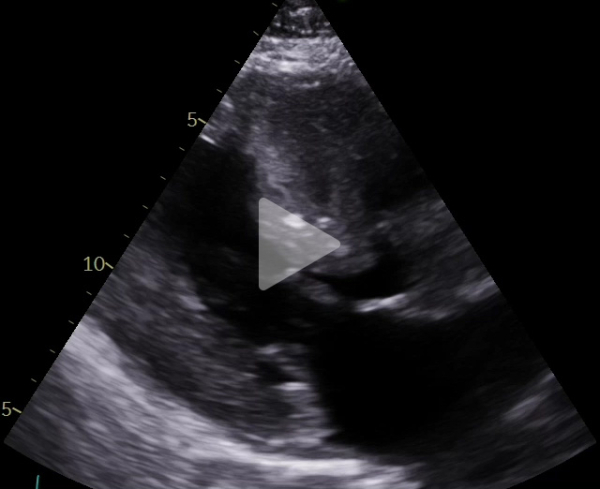

Voici son échocardiographie

Vidéo 1 : échocardiographie 2D en incidence parasternale grand axe